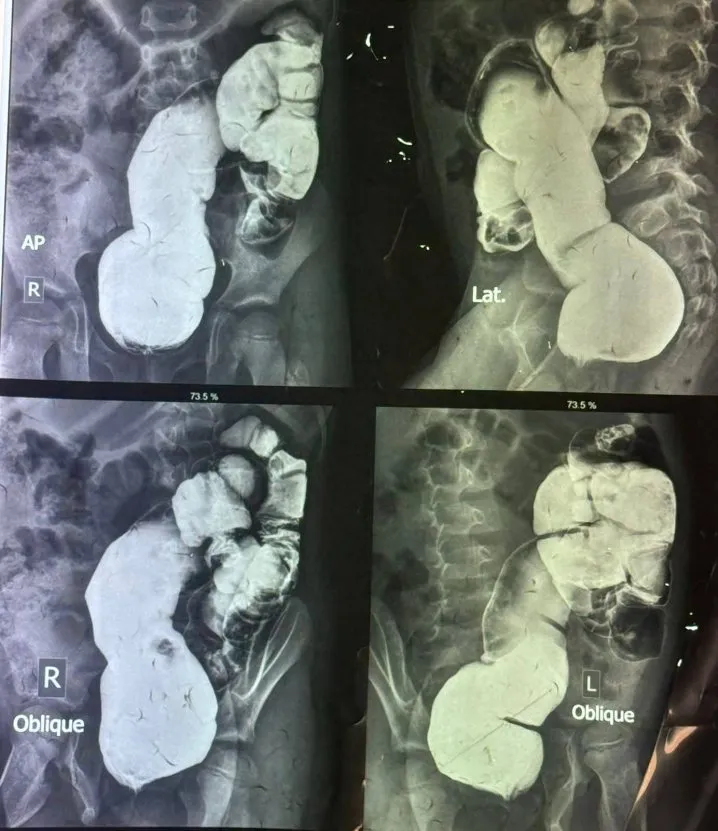

أجرى الأستاذ الدكتور علي عكاب جودة ( رئيس فرع الجراحة في كلية الطب / الجامعة المستنصرية – إستشاري جراحة الأطفال وحديثي الولادة ) عملية جراحية نوعية استئصال القولون السيني لطفل يبلغ من العمر 5 سنوات في مستشفى الطفل المركزي التعليمي في مستشفى الطفل المركزي التعليمي .

وذكر رئيس الفريق الطبي الجراحي الدكتور علي عكاب جودة : تم إجراء عملية نوعية استئصال القولون السيني مع تفويه القولون النازل لطفل يبلغ من العمر 5 سنوات كان يعاني من امساك مزمن (Dolichsigma) لم يستجب للعلاج التحفظي ، وبعد الفحص السريري والتحاليل المختبرية ، أجريت العملية الجراحية تحت التخدير العام، وتكللت العملية بالنجاح وأُخرج الطفل بعد إكتسابه للشفاء التام.